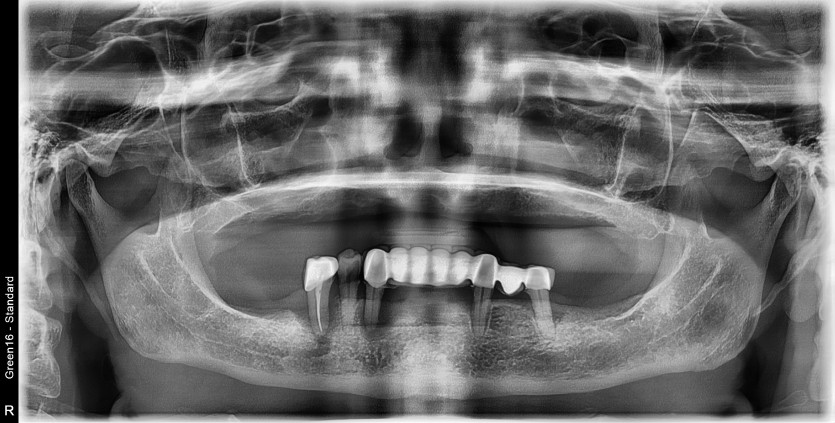

만 60세 전체 임플란트 증례

전체 임플란트 증례입니다.

16개의 임플란트로 완성하였습니다.